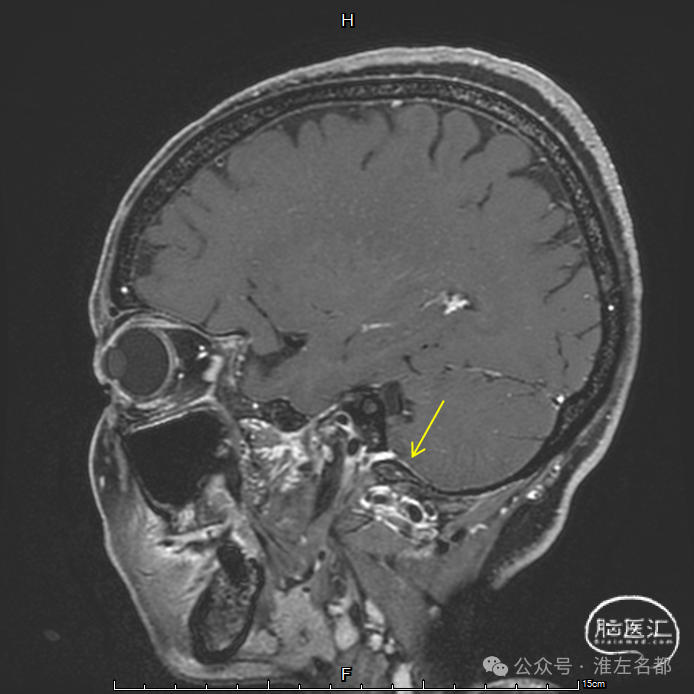

三维黑血高分辨T1

三维黑血高分辨T1平扫(上图)和增强(下图):右侧乙状窦慢性血栓,平扫呈等低信号,并显著强化。

三维黑血高分辨T1平扫(上图)和增强(下图):右侧横窦慢性血栓。

三维黑血高分辨T1平扫(上图)和增强(下图):上矢状窦慢性血栓;直窦内新进血栓(急性血栓等低信号,或亚急性血栓高信号,无强化)。

三维黑血高分辨T1平扫(上图)和增强(下图):左侧横窦发育细小。

三维黑血高分辨T1平扫(上图)和增强(下图):左侧乙状窦局部未发育。